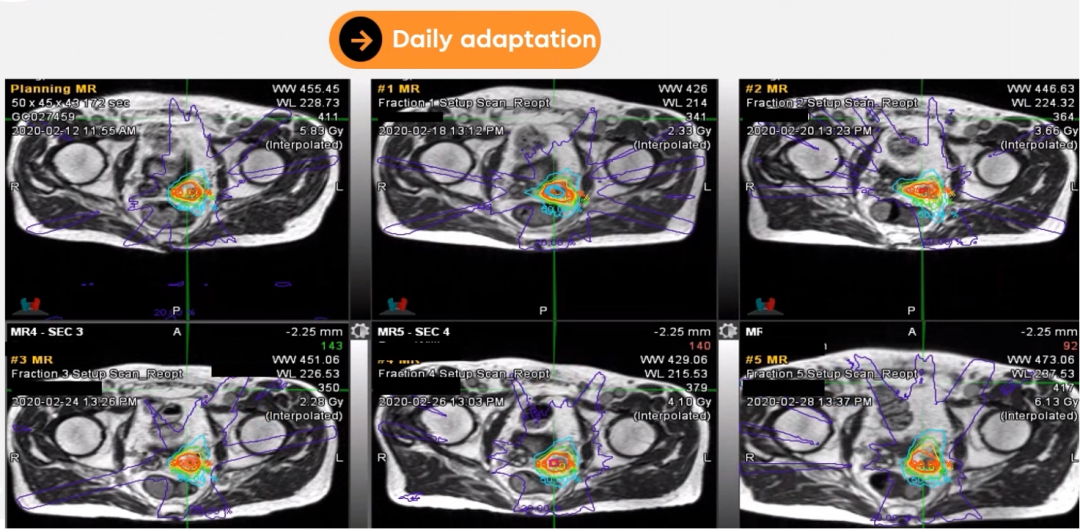

ÖðÈÕ×Ô˳Ӧ£ºMRIdianÔÊÐíÓû§ÔÚÖðÈÕÖÎÁÆÊ±¾ÙÐÐMRIɨÃ裬£¬£¬£¬£¬£¬Òò´Ë¿ÉÒÔ¿´µ½Ö×ÁöºÍΣ¼°Æ÷¹Ù£¨OAR£©ÐµÄÐÎ×´ºÍλÖ㬣¬£¬£¬£¬£¬¿ÉÒԾݴËÀû±ãµØµ÷½âÂÖÀª¹´»ºÍÔÚÏß×Ô˳ӦÍýÏë¡£¡£¡£¡£¡£¡£¡£

ͨ¹ýչʾһλ×ó²à¾«ÄÒÏÙ°©µÄÔʼÍýÏëºÍÖðÈÕ×Ô˳ӦÍýÏ룬£¬£¬£¬£¬£¬ÇåÎúÏÔʾÁ˰ÐÇøºÍΣ¼°Æ÷¹ÙÔÚÿ´Î·ÅÁÆÊ±¾ùÓнϴóת±ä£¬£¬£¬£¬£¬£¬Í¨¹ýMRIdianÔÚÏß×Ô˳Ӧ¹¦Ð§£¬£¬£¬£¬£¬£¬¿ÉÒÔÔڽϺéÁ÷ƽÉÏÐÞÕýÕâЩת±ä£¬£¬£¬£¬£¬£¬ÔÚ×öµ½¸øÓè°ÐÇø¸ß¼ÁÁ¿µÄͬʱ£¬£¬£¬£¬£¬£¬¾¡¿ÉÄܵÄïÔÌΣ¼°Æ÷¹ÙµÄ¼ÁÁ¿¡£¡£¡£¡£¡£¡£¡£

Dr. CamilleriÌåÏÖǰÏßÏÙ·ÅÁƵķִμ䣬£¬£¬£¬£¬£¬Ç°ÏßÏÙµÄÒÆ¶¯¶È²»Ëã´ó£¬£¬£¬£¬£¬£¬µ«¾«ÄÒÏÙµÄÒÆ¶¯¶È½Ï´ó£¬£¬£¬£¬£¬£¬¿ÉÒÔµÖ´ï5mm×óÓÒ£¬£¬£¬£¬£¬£¬Í¨¹ýMRIdianÖðÈÕÔÚÏß×Ô˳ӦÍýÏëµ÷½â¿ÉÒÔÐÞÕýÕâЩÔ˶¯¡£¡£¡£¡£¡£¡£¡£